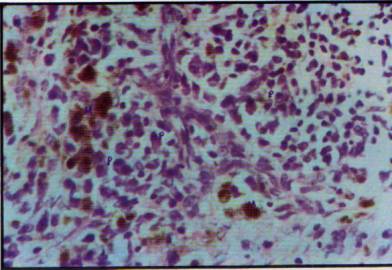

Foto

13: Estroma conectivo y neovascular con discreto infiltrado por células

14: Con fondo de infiltrado leucocitario mononuclear neovasos, se observan macrófagos

cargados de pigmento hemosiderinico (M) y células plasmáticas maduras (P)

Algunas áreas del sector fibroso limitante mostraron además de la

presencia de macrófagos con restos fagocíticos de hemosiderina, la afluencia

de algunos plasmocitos con evidencias de marcada actividad secretoria y

disposición foca] agrupada (foto 14).